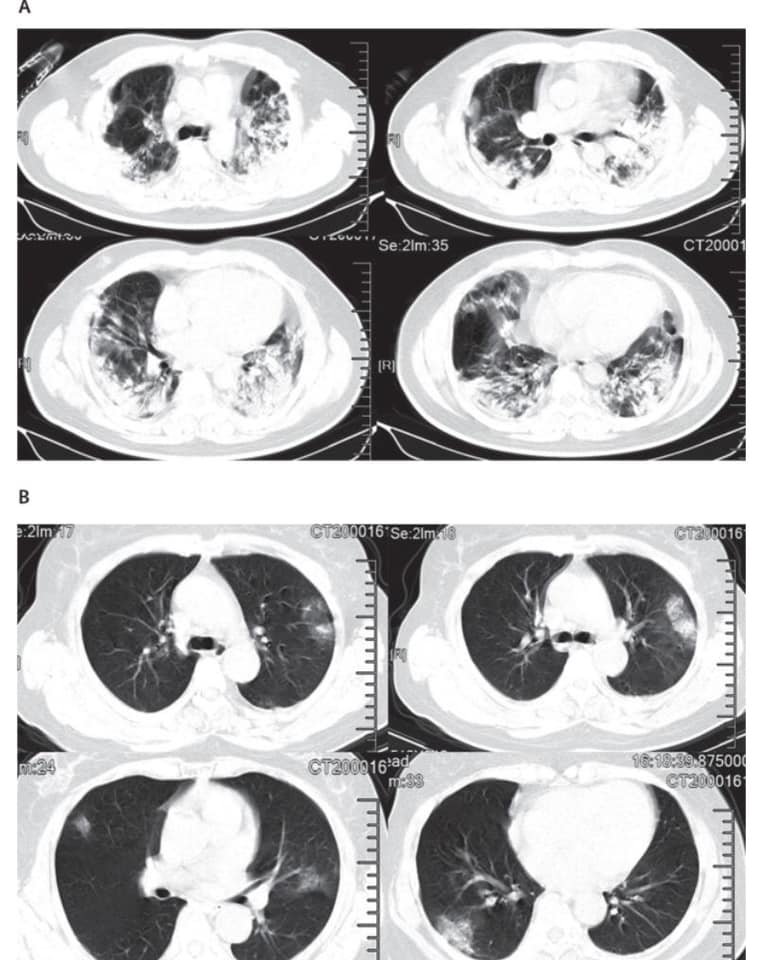

COVID-19新冠肺炎的重症与危重症,看了CT的肺绝对捏出一把冷汗,如今我们现在已经成功解剖了好几个死亡病例的遗体。

看见遗体的肺,连经验丰富的法医都被吓坏,遗体的肺根本已经彻底报废,里面都是粘液。所以说,患者死亡之前,是完全不能呼吸空气、乱喊乱叫,好像被水淹死的感觉!